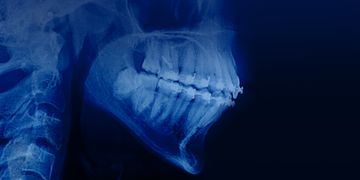

Ортодонтия у пациентов с патологией пародонта и костной ткани

Урок 1.Элайнер-терапия пациентов с заболеваниями пародонта

Урок 2.Как ортодонтическое лечение может улучшить результаты протезирования

Урок 3.Ортодонтическое лечение у взрослых пациентов с пародонтитом

Урок 4.Дистализация моляров нижней челюсти: лечение сложных случаев скученности и мезиального прикуса без удаления зубов

Урок 5.Ортодонтия как фактор расширения возможностей имплантации и протезирования

Урок 6.Лечение глубокого прикуса у взрослых пациентов: научно-доказательный подход

Урок 7.Лечение взрослых пациентов с открытым прикусом и вертикальным типом роста

Урок 8.Ортодонтическое лечение взрослых с помощью системы Damon

Урок 9.Клинические аспекты ортодонтического лечения взрослого пациента с вторичным неправильным прикусом и патологической стираемостью

Урок 10.Ортодонтическая экструзия для восстановления сильно разрушенного зуба

Урок 11.Элайнер-терапия взрослых пациентов: опыт профессора